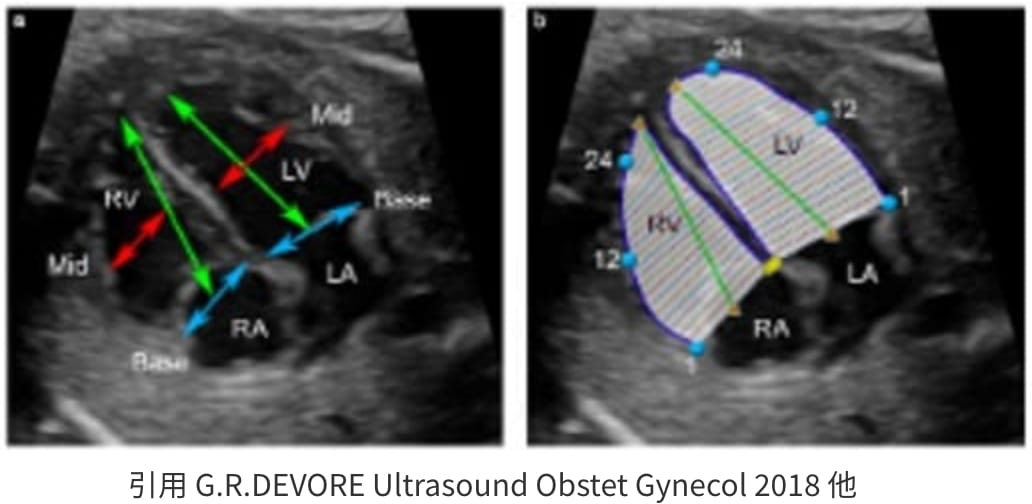

Fetal HQ

Fetal HQ®はSpeckle-Tracking法を用いて胎児心室壁の運動を解析する方法です。Speckle-Tracking法とは心筋の断層エコー画像上の小斑点(speckle)を追跡し心筋局所の機能を解析する方法で、成人の心臓超音波検査でも用いられています。一回数秒の動画の保存で複数の心機能が同時に評価できる新しい検査法です。

Fetal HQで測定できる項目

Sphericity index(SI)

心室の形態を定量化する。SIは四腔像における短軸径に対する長軸径の比率として表され、心尖部〜心基部を長軸に直交する24のsegmentに分け、segmentごとのSIを算出できる。1に近づくほど球形であると言える。

- 成人では心不全が増悪するほど心室内腔形が球形に近づく。

Fractional shortning

(拡張末期径−収縮末期径)/拡張末期径×100で表され、短軸で収縮能を評価する。SegmentごとにFSを算出できる。

Fractional area change

(拡張末期面積–収縮末期面積)/拡張末期面積×100で表され、面積で収縮能を評価する。

Global strain

(収縮末期心室内周長−拡張末期心室内周長)/拡張末期心室内周長×100で表され、心筋全体のストレイン(伸び縮み)を数値化することで心筋の三次元的な動きを評価する。

Fetal HQの臨床における活用はまだ限定的です。当院では先天性心疾患の胎児や、双胎間輸血症候群・胎児胸水・胎児貧血といった胎児治療が必要な胎児の心機能を評価するために、従来用いられている心機能の評価項目に加え、Fetal HQを用いて心エコー検査を行っています。データを積み上げ、Fetal HQの活用の幅を広げていきます。